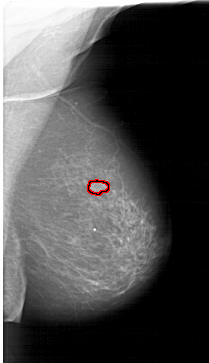

A_1261_1.RIGHT_MLO

RIGHT_MLO LINES 6526 PIXELS_PER_LINE 3751 BITS_PER_PIXEL 12 RESOLUTION 43.5 OVERLAY

FILE: A_1261_1.RIGHT_MLO.OVERLAY

TOTAL_ABNORMALITIES 1

ABNORMALITY 1

LESION_TYPE MASS SHAPE LOBULATED MARGINS CIRCUMSCRIBED

ASSESSMENT 4

SUBTLETY 5

PATHOLOGY MALIGNANT

TOTAL_OUTLINES 1

BOUNDARY